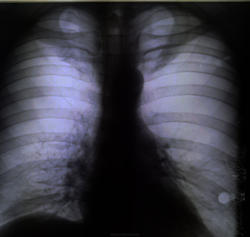

Непосредственно сама история: Пациент С. 35 лет. не курит. В детстве часто болел простудными заболеваниями. Обратился к участковому терапевту с жалобами на появившуюся одышку, общую выраженную слабость, "отсутствие сил". Направлен на флюрографию: был поставлен ошибочный диагноз "двусторонняя нижнедолевая пневмония". Назначен ударный курс антибиотиков. Облегчения никакого, у больного апатия, и навязчивая идея что он болен туберкулезом. Флюрография повторнопосле лечения, которую как раз мне и довелось описывать. Очень зацепил легочной рисунок!

в рекомендациях написал КТ-исследование ОГК. В виду интересности случая попросил участкового терапевта взять  ситуацию на контроль, чтоб пациент "не пропал". Больному дали талон на КТ, но каким то чудом Начмед больницы узнал, что из поликлиники больного прямиком направляют на КТ минуя классическую рентгенографию... Основываясь на своих доводах администратора и усмехнувшись (в прямом смысле слова) когда читал написаный мной дифференциальный ряд, заставил сделать обзурную рентгенограмму

ОГК в прямой и боковой проекции, результат тот же что и на флюшке: